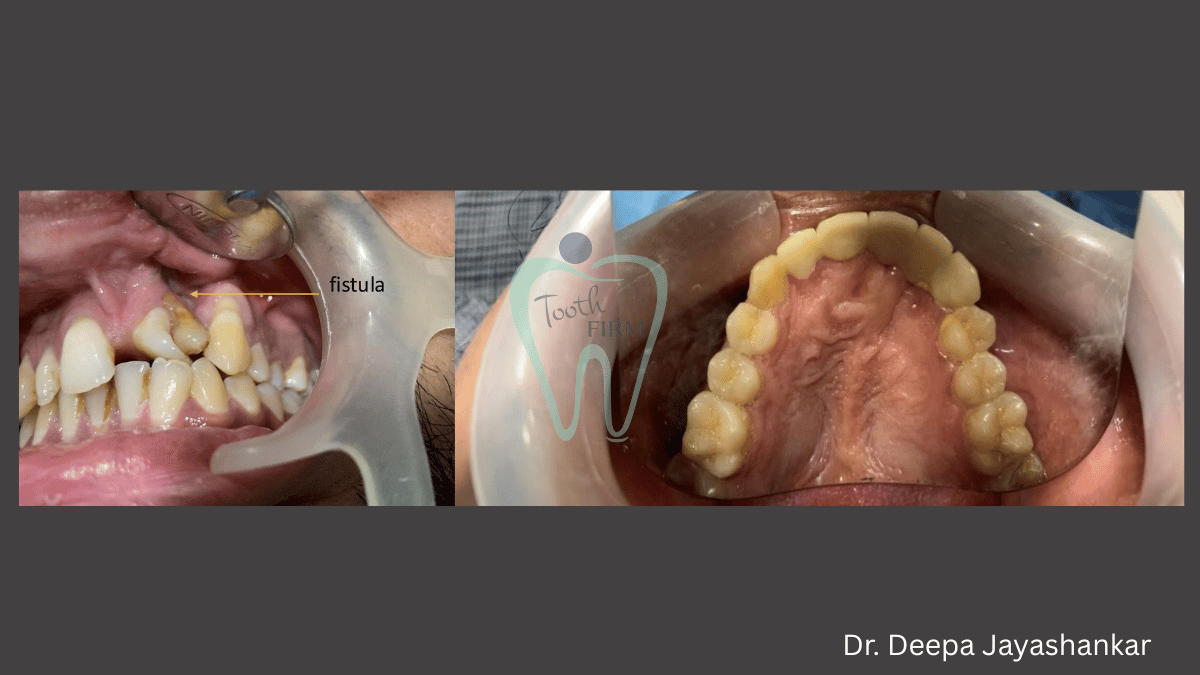

Cleft Lip and Pallet Rehabilitation